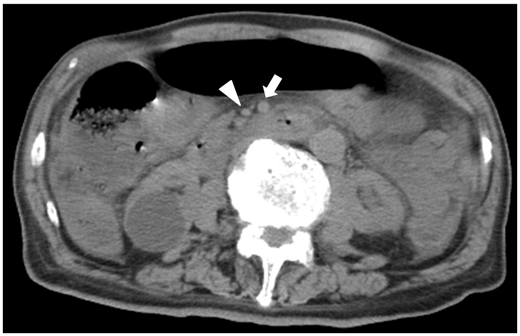

タイトルは「多発肝動脈瘤破裂による胆道出血を来したANCA関連血管炎の1例」

絞扼性イレウスやNOMI、そして今回の投稿症例である上腸間膜動脈閉塞症など腸管虚血を来たす疾患では、腹膜刺激徴候を伴わない激烈な疼痛(腸管穿孔に至っていない場合)を来たすのが特徴です。造影CTを撮影しなければ診断できない場合が多いのですが、単純CTしかとれない場合でも有用な所見として今回Acceptされた「Smaller SMV sign」があります。本来ならばSMA径のほうが細くなるのですが、静脈系の還流障害でSMVへの血流流量が減少し、SMA径に比べてSMV径が小さくなる逆転現象が起きます。